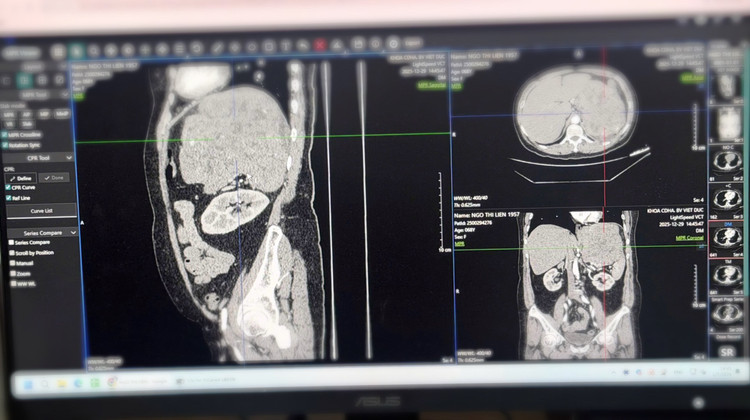

Hình ảnh phim chụp khối u kích thước 20cm của bệnh nhân - Ảnh BVCC

Sau khi thăm khám, hội chẩn và đánh giá kỹ lưỡng bằng các phương tiện chẩn đoán hình ảnh hiện đại, các bác sĩ đã chỉ định phẫu thuật cắt bỏ khối u sau phúc mạc.